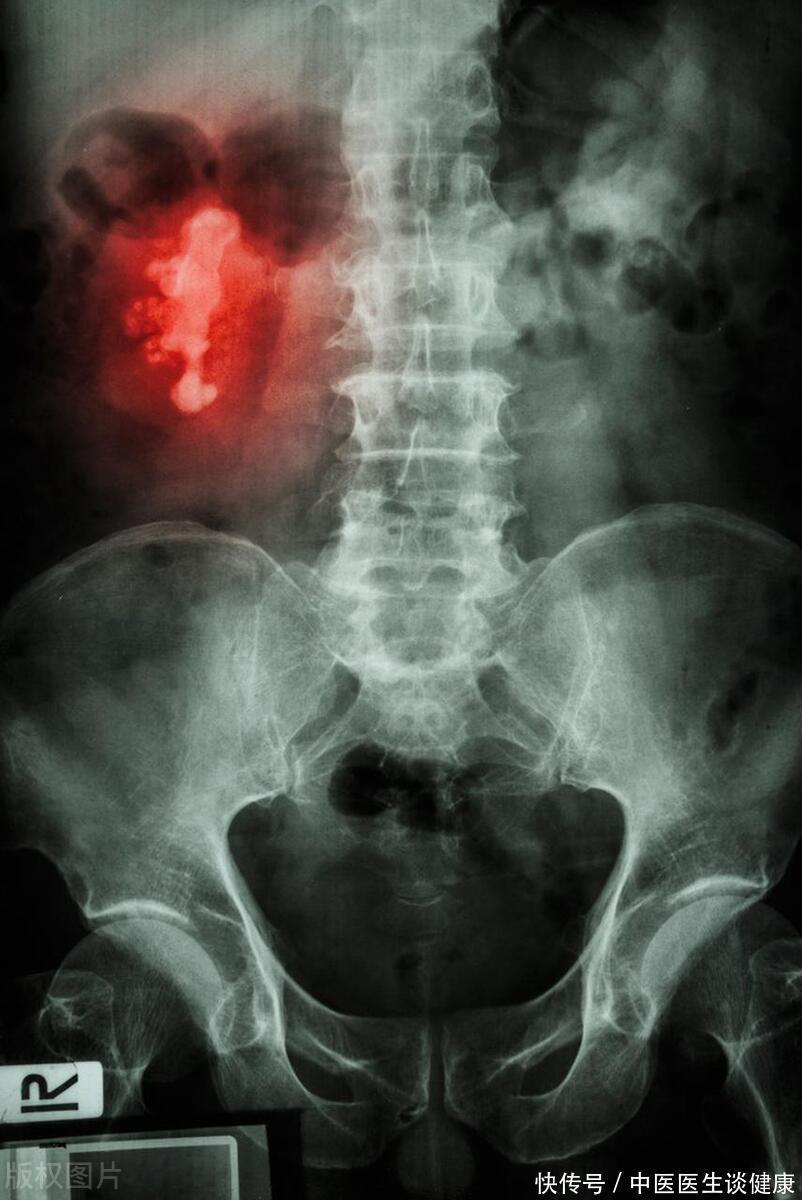

欲答王先生疑虑,需先窥肾结石由来。必先探究者,方能解其迷。肾结石的形成与多种因素有关,其中饮食习惯是一个重要方面。茶叶内含草酸,其与钙结合后可生成草酸钙结石,此为肾结石之一。但是,这并不意味着喝茶就一定会导致肾结石。实情是,肾结石的生成是一项错综复杂的过程,牵涉多方面因素的综合影响,纷繁交错。

最后,对于已经患有肾结石的人来说,过量饮用茶叶可能加重病情。茶叶中的草酸与钙相遇,宛如引发草酸钙结石的化学盛宴,使得肾脏负担更加沉重。

张阿姨是一位退休老人,平日里喜欢品茶养生。最近她却因为双肾结石而住进了医院。医生告诉张阿姨,她的肾结石与长期过量饮用浓茶有关。原来,张阿姨每天都要喝上几壶浓茶,而且喜欢空腹喝茶。长期下来,茶叶中的草酸与体内的钙结合形成了草酸钙结石,堵塞了尿路,引发了剧烈的疼痛。